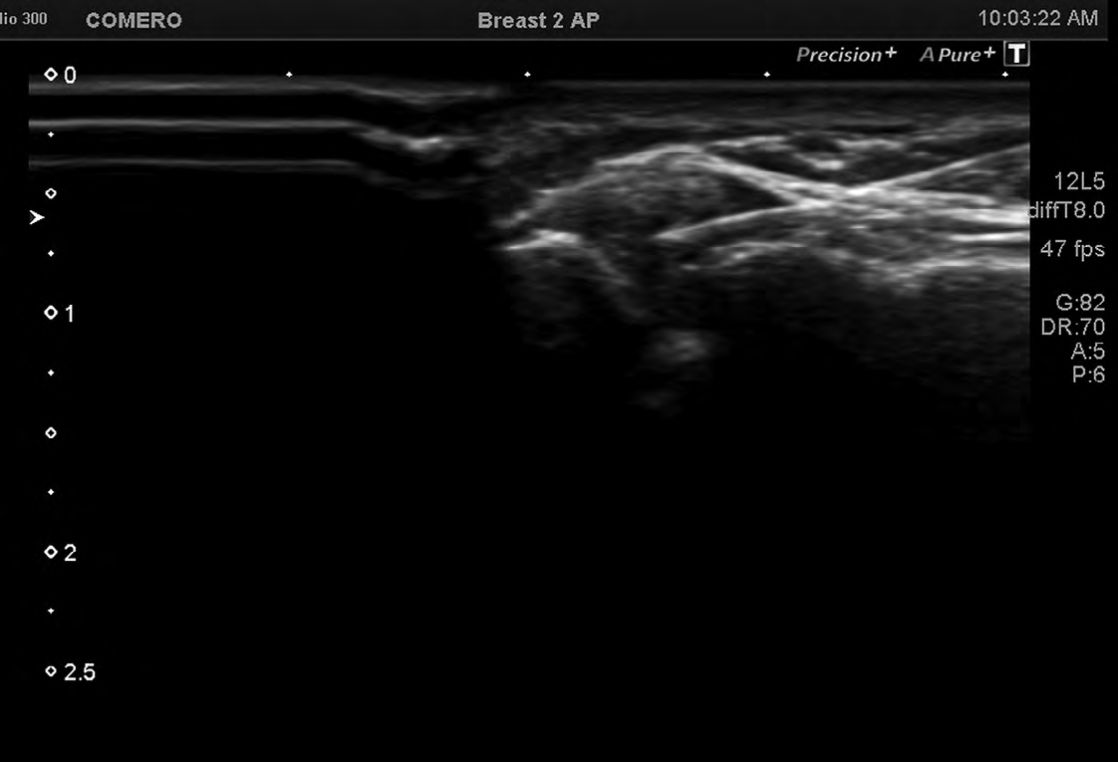

Foto 2

Punta de la aguja dentro la vaina de la PBL. Existe un sector ecogénico en la parte superior producido por pequeñas cantidades de aire que pasaron inadvertidamente junto con los fármacos inyectados.

El trayecto de la aguja es el correcto, desde el sector lateral al medial, evitando puncionar los vasos arteriales circunflejos.

La infiltración de la PLB, se realizó también en decúbito supino, con visualización de la misma en un plano transverso y aproximación lateral hacia medial, con empleo de doppler color, de manera de identificar la arteria circunfleja anterior y evitar punciones accidentales. (5-11)